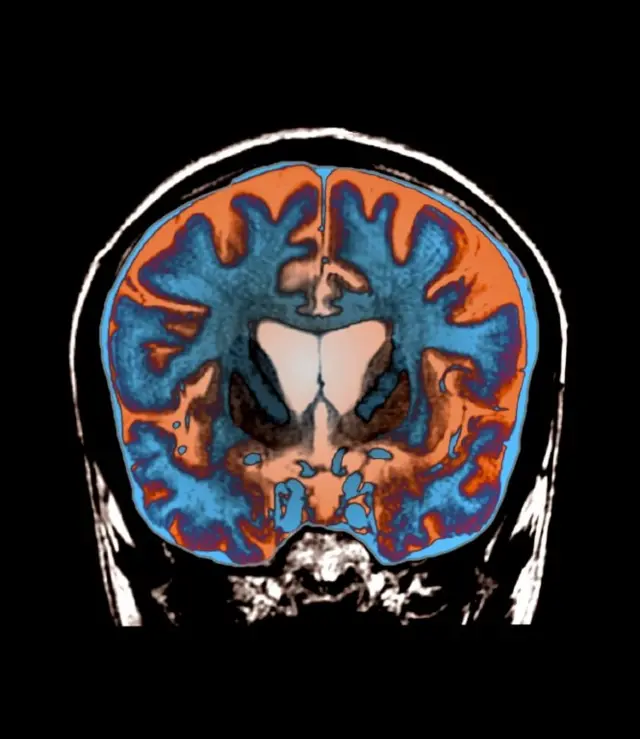

در بیماری هانتینگتون مرگ غیر قابل مهار سلولهای مغز سبب می شود وضعیت بیمار از نظر حرکت، رفتار، حافظه و توان فکر کردن مرتبا رو به وخامت برود.

این بیماری بعلت اشکالی در بخشی از دیانای ایجاد می شود که به آن ژن هانتینگتین می گویند. این ژن مسئول تولید پروتئینی است به نام هانتینگتین که برای مغز ضروری است. اما نقص ژنتیکی باعث معیوب شدن پروتئین و پروتئین معیوب باعث تخریب سلولهای مغز میشود.